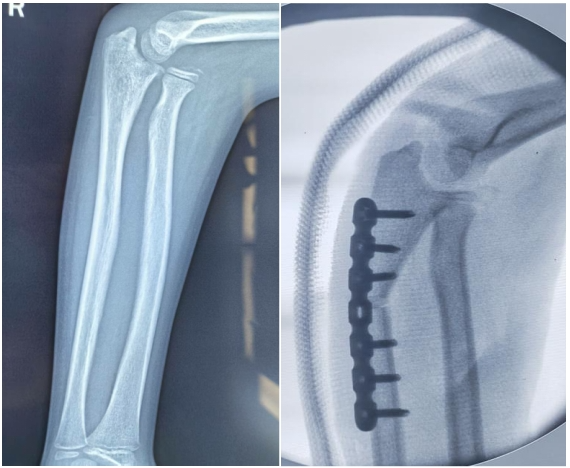

近日,济宁市第一人民医院小儿外科为一名11 岁陈旧性孟氏骨折患儿成功实施手术治疗,术后患儿恢复良好,已顺利出院。孟氏骨折是累及尺骨上 1/3 骨折合并桡骨头脱位的复杂损伤,目前通常将受伤超过4周的称为陈旧性孟氏骨折,此类患者常面临解剖结构紊乱、复位固定困难及并发症风险高等,给外科治疗带来挑战。

面对这一棘手病情,济宁市第一人民医院小儿外科迅速组织病例讨论。经详细评估,患儿因陈旧性孟氏骨折已出现桡骨头长期脱位、尺骨畸形愈合,传统保守治疗难以实现解剖复位与稳定固定。专家团队一致决定采用切开复位尺骨截骨矫形钢板内固定、桡骨头复位、环状韧带修复的治疗方案。

手术当日,由小儿外科科主任庄博主刀,苏涛、孔令启医师协助,在麻醉科与手术室团队的密切配合下有序开展。凭借丰富经验与精湛技术,依次完成尺骨截骨矫形钢板固定、桡骨头复位及环状韧带修复。整个过程操作精细,术后影像学检查显示桡骨头复位稳定,患儿生命体征平稳。

小儿外科主任庄博表示:“陈旧性孟氏骨折的治疗不仅需要实现肱桡关节解剖复位、改善尺骨畸形愈合和恢复尺骨长度,降低神经损伤风险,更要关注患儿的远期功能恢复。”